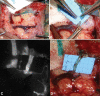

Millions of people worldwide suffer from lymphedema. In developed nations, lymphedema most commonly stems secondarily from oncologic treatment, but may also result from trauma. More recently, lymphedema has been identified in patients after gender-affirmation phalloplasty reconstruction. Regardless of the etiology, the underlying pathophysiology involves blockage of lymphatic flow, resulting in lymph stasis, thus triggering a cascade of inflammation culminating in fibrosis and adipose deposition. Recent technical advances led to the refinement of physiologic and reductive surgeries-including lymphovenous anastomosis and free functional lymphatic transfer, which collectively encompass a variety of flap procedures including lymph node transfer, lymph channel transfer, and lymphatic system transfer. This article provides a summary of our approach in the assessment and management of the lymphedema patient, including detailed intraoperative photography and imaging, in addition to advanced technical considerations in physiologic reconstruction.